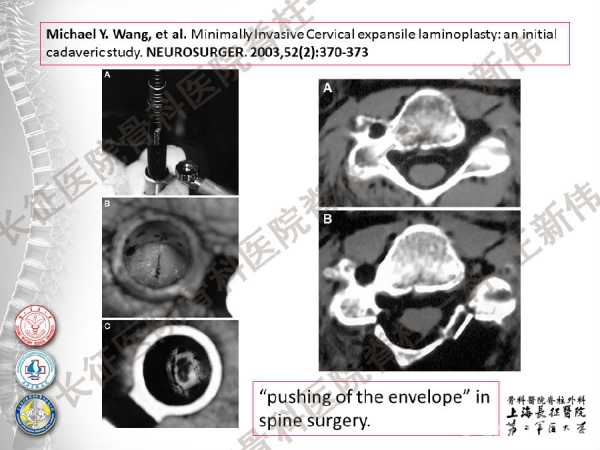

王新伟:颈椎后路通道下手术病例报告及文献回顾

颈椎后路通道下手术有哪些?颈椎后路通道下手术能做哪些事?颈椎后路通道下手术有哪些优势?长征医院骨科医院脊柱一科王新伟副教授通过临床病例报告及文献回顾,给出了他的答案——